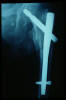

Fractura intertrocantérea de fémur, osteosíntesis